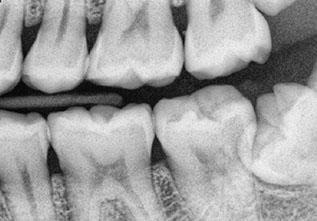

BITEWING RADIOGRAPHS

Bitewing radiographs are indicated primarily to detect or monitor hidden caries in the interdental tooth surfaces. Very useful for a dentist, as the proximal surfaces of the teeth cannot be visually examined or clinically accessible with dental explorers.